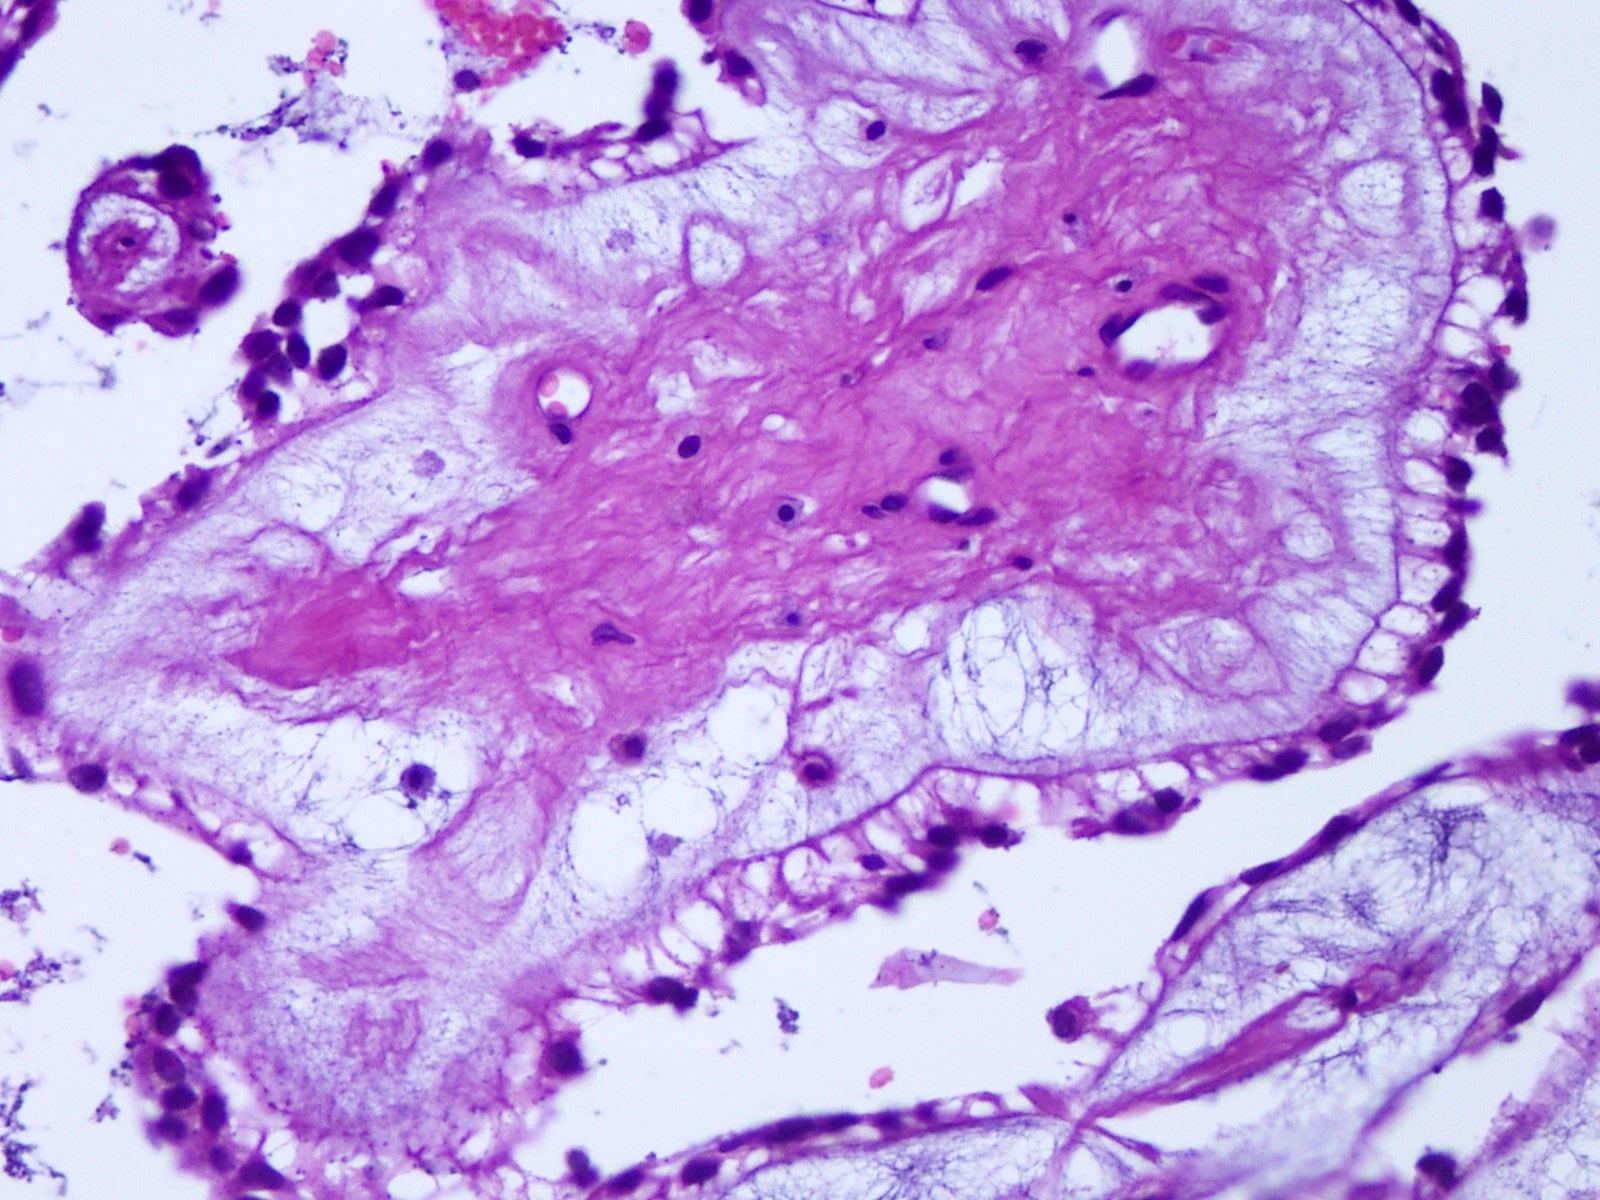

- Intraoperative squash / smear preparation and frozen section reveals epithelioid to spindled tumor cells arranged around microcysts and forming papillary structures with perivascular myxoid change; these features are diagnostic in the appropriate clinical setting

Microscopic (histologic) description

- Most common pattern is radial arrangement of cuboidal to epithelioid elongated glial tumor cells around hyalinized fibrovascular (central, often hyalinized blood vessels) cores in a papillary configuration

- Accumulation of basophilic myxoid material around blood vessels (myxoid stroma) and in microcysts

- Myxoid material is highlighted by PAS and Alcian blue positive staining

- Occasionally tumor cells show distinctive eosinophilic balloons; these are PAS positive spherules that demonstrate spiculated reticulin staining (Am J Surg Pathol 1996;20:1091)

Microscopic (histologic) images